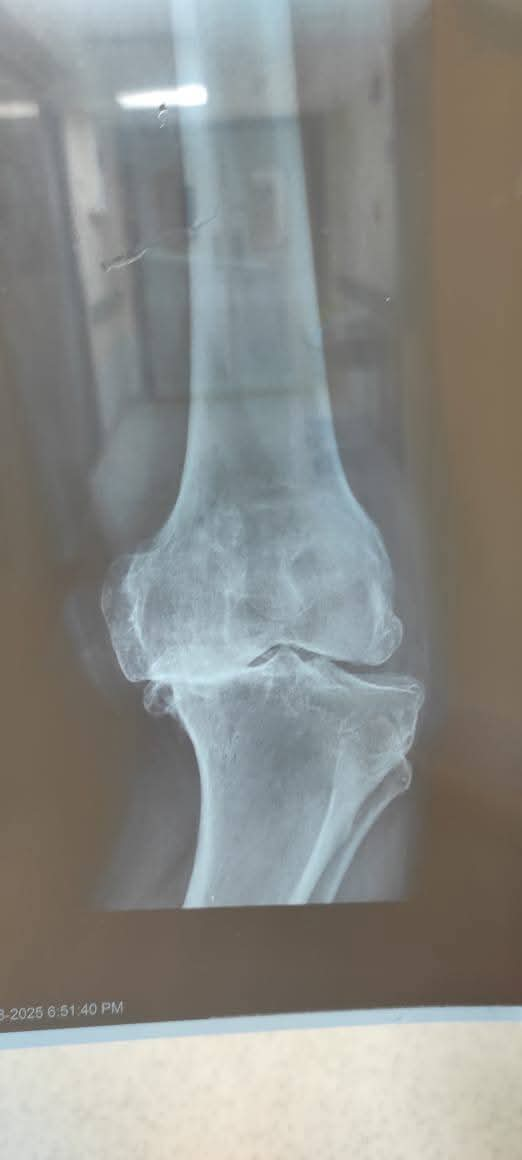

حقق الفريق الطبي بمستشفى القنطرة شرق التابعة لفرع الهيئة العامة للرعاية الصحية في محافظة الإسماعيلية، إنجازًا جديدًا بإجراء عملية دقيقة لاستعدال الركبة وتركيب مفصل ركبة كامل أسمنتي ذي جذع طويل (Long Stem) لمريض يبلغ من العمر 56 عامًا، بعد معاناة طويلة من خشونة متورمة وتشوه شديد بالخارج للركبة اليسرى، وهي من الحالات المتقدمة التي تتطلب مهارة عالية وخطة جراحية دقيقة.

وكان مريض في الستينات من عمره حضر إلى مستشفى القنطرة شرق، وهو يعانى من خشونة متورمة بالركبة اليسرى مع تشوه شديد.

وخلال الجراحة، نجح الفريق في استعدال المحور التشريحي للساق وتصحيح التقوس، ثم تركيب المفصل الصناعي المزود بجذع طويل لضمان الثبات والدعم في الحالات المتقدمة.